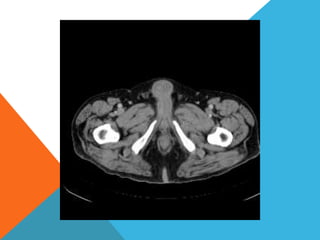

El paciente presentó síntomas de sangrado digestivo y pérdida de peso. Exámenes revelaron gastritis crónica asociada a H. pylori. Un tumor fue descubierto en una colonoscopia normal. La cirugía removió un tumor fibroide solitario, una rara neoplasia mesenquimal que usualmente crece lento y tiene bajo potencial de malignidad. El pronóstico después de la remoción quirúrgica es generalmente bueno.